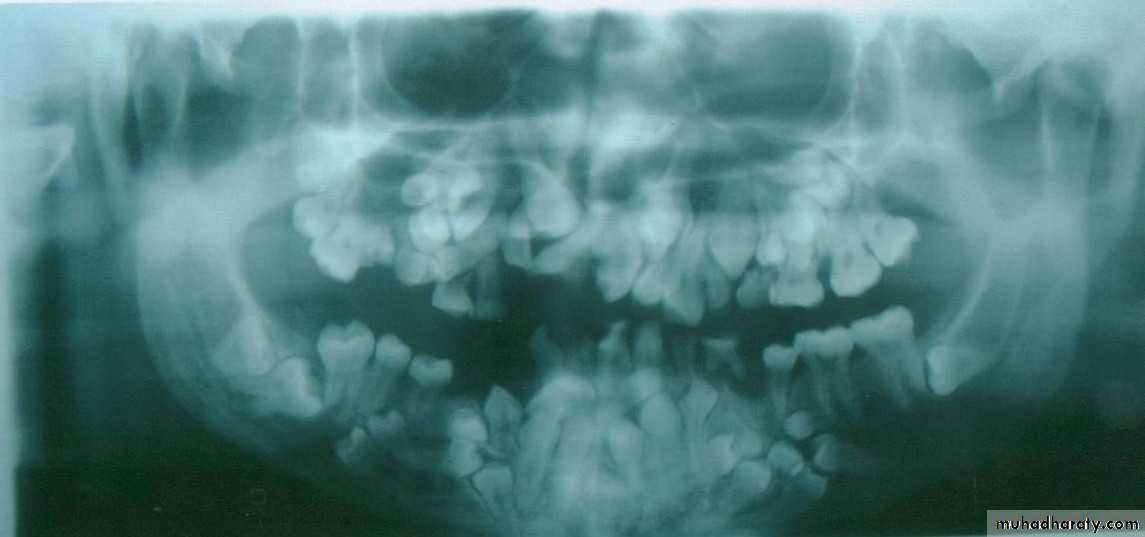

Systemic causes of impaction1- Hereditary syndromes like cliedo cranial dysostosis , downs syndrome ,etc…2- Endocrinal deficiency like hypothyroidism and hypopituitarism3- Febrile diseases (brucellosis , scarlet fever,…etc)( all systemic causes is usually associated with multiple teeth impaction)

Local causes of tooth impaction1 – Prolonged retention of deciduous teeth

2 – Arch length deficiency with large sized teeth(arch –tooth discrepancy)

3 – Odontogenic cyst or tumor change the path of eruption(pathology)

4- Cleft lip and cleft palate

5- Dense overlying bone or thick fibrous soft tissue(due to chronic inflammation)

6- Abnormal root pattern( dilacerated or curved or bulbous…etc )